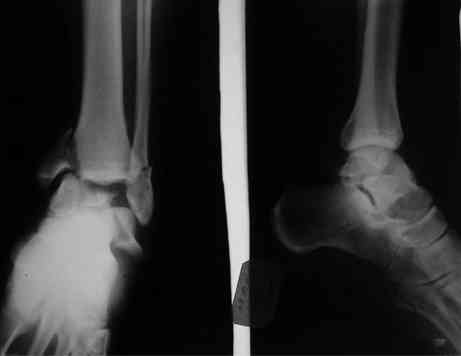

Interesting case

The ankle joint looks ruined. I wonder howcome is it as ruined after 2 days. I would open the joint( Some people would artroscope it) and judge the osteosynthes vs ankle fusion according to the ankle joint condition. The subtalar does not look injured, but if you feel there is a clinical

problem- CT it. Above all- when I see such an X-Ray I call the resident who ordered it and tell him that I would expect him first thing to reduce it on arrival since the soft tissue suffer and I hope that currently the p-nt is reduced to some extent at least.

Sorry- I revised it and the talus is fractured- take him to the theater at once and reduse it with Int Fix

The soft tissue will be a problem- Ex Fix will be better thn plaster

Какая именно травма тарана?

Подробней, пожалуйста!

а основании двух видов ренгенограмм невозможно радикально решить о необходимости открытой репозиции или первичного артродеза.

Для оценки состояния нужны дополнительные исследования, например Canale или Broden ренгенограммы и Компьютерная томография.

При переломах тарана всегда имеется риск AVN, а классификация Hawkins поможет разобраться с предполагаемыми осложнениями.

Если в первом типе, когда перелом шейки без смещения, тогда AVN менее 10%, при втором типе когда имеется смещение и вывих тарана в субталарном сочленении меньше 40%, а при типе III когда смещение в голеностопном и субталарном суставах - около 90% и в типе IV, когда происходит полный вывих, риск AVN достигает 100%.